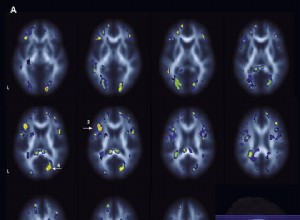

Syndrome de fatigue chronique : une inflammation cérébrale en cause ? Étude japonaise révélatrice

Chimiothérapie et mémoire : des effets durables sur le cerveau des survivants du cancer

L'anesthésie générale chez les bébés : un impact potentiel sur la mémoire à long terme